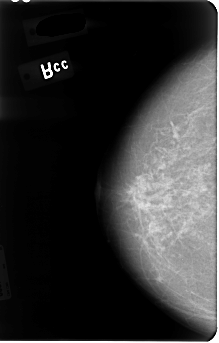

B_3046_1.LEFT_CC

LEFT_CC LINES 4824 PIXELS_PER_LINE 3352 BITS_PER_PIXEL 12 RESOLUTION 50 OVERLAY